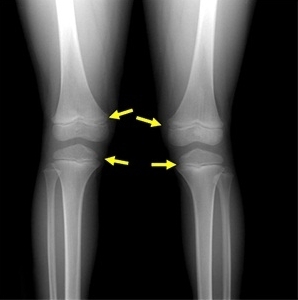

3. 키 크는 운동: 성장판 자극하는 활동 & 올바른 자세

운동은 성장판을 자극하고 성장 호르몬 분비를 촉진하여 키 성장에 긍정적인 영향을 미칩니다. 🤸♂️

- 점프 운동: 줄넘기, 농구, 배구, 점프 스쿼트 등 성장판에 가벼운 충격을 주는 점프 운동이 좋습니다.

- 스트레칭 & 매달리기: 성장판을 늘려주는 스트레칭이나 철봉에 매달리는 운동도 키 성장에 도움을 줍니다.

- 올바른 자세: 평소 구부정한 자세는 키 성장을 방해할 수 있습니다. 바른 자세를 유지하는 습관을 들여야 합니다.